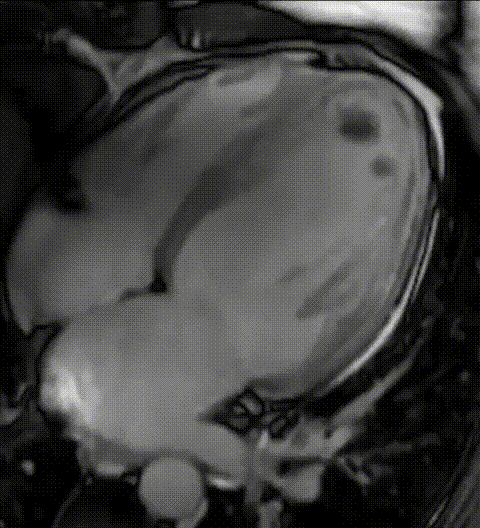

Imagem da Semana

Está ruim de trombo esse aí? Observe esses trombos intracavitários no ápice do VE identificados na ressonância magnética cardíaca após IAMcSST anterior extenso.